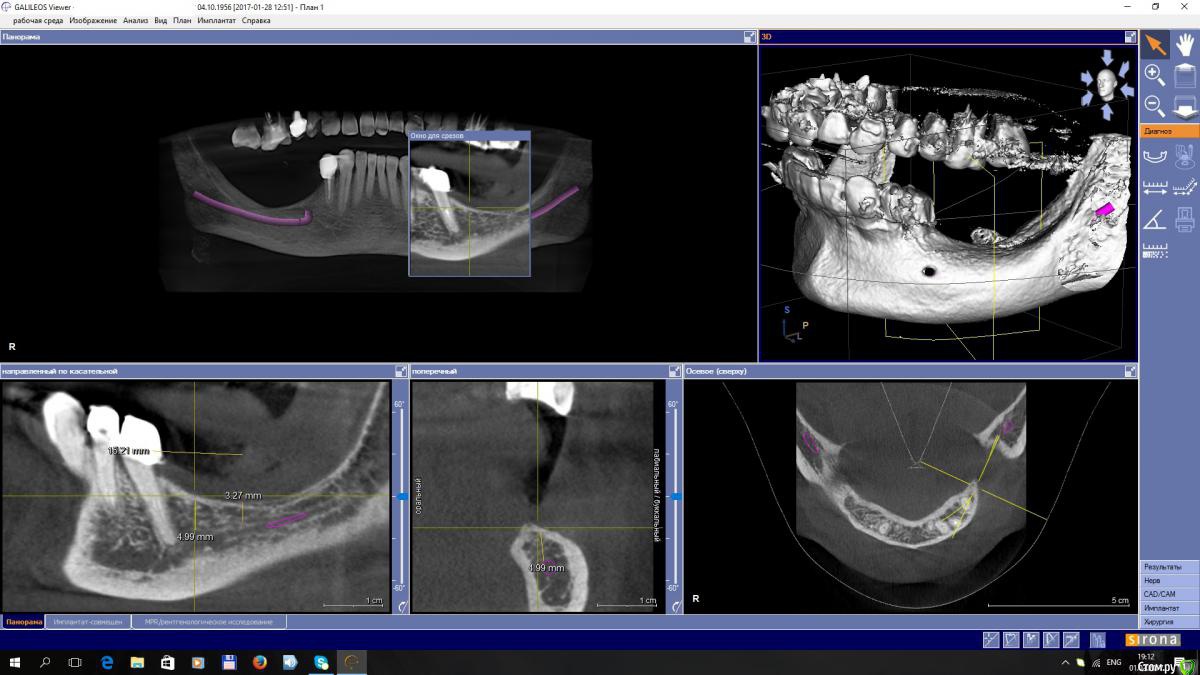

EEcho Опубликовано 3 февраля, 2017 Поделиться Опубликовано 3 февраля, 2017 Уважаемые коллеги! Я в раздумье.Максимально, кость я могу поднять на 4-5 мм, с одной и с другой стороны. Дальше не позволяет межальвеолярная высота.Делать репозицию нерва или все таки пластику с последующей постановкой коротких имплантов. Ссылка на комментарий

syrovovec Опубликовано 12 февраля, 2017 Поделиться Опубликовано 12 февраля, 2017 Больше за латерализацию, но постановку сбоку канала тоже рассмотреть можно Ссылка на комментарий